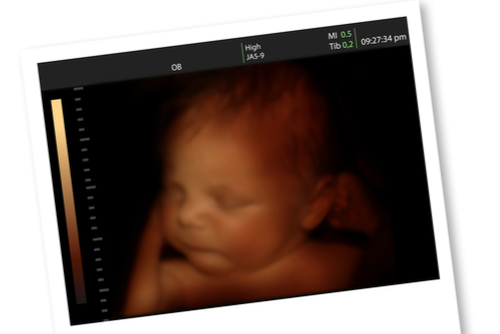

妊婦健診の楽しみのひとつが、赤ちゃんの「今」がわかるエコー写真ですよね。ここではエコー写真の特徴を見ていきましょう。

胎児の状態では、見た目の大きさで時系列を判断するのも難しいですよね。保存して順番に並べておけば、赤ちゃんの成長がわかりやすくなりますよ。

保存状態を良くしておけば、ママだけではなくパパや祖父母も楽しく見返すことができますよ。赤ちゃんが大きくなったときに見せてあげるのも素敵ですね。